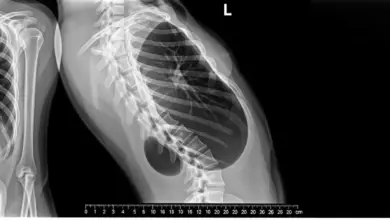

- Radiografias da coluna: permitem visualizar a forma das vértebras, medir o ângulo da curva e acompanhar a evolução ao longo dos anos.

- Exames de função pulmonar: indicados em curvas torácicas importantes para medir o impacto respiratório.